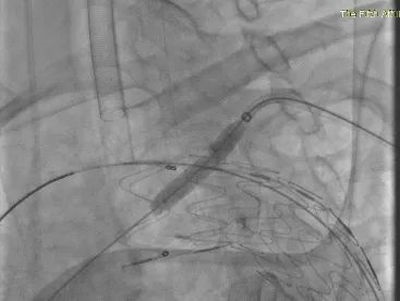

▲ 球囊扩张穿刺口

手术方式确定后,快速完成术前准备,在全麻下行在其胸主动脉植入覆膜支架,同时在左锁骨下动脉原位开窗,植入分支支架。体内开窗完成仅用几秒钟,整个手术过程耗时2小时,患者只是在右股部开2mm的穿刺口和左上肢3cm的切口。术后,患者意识清醒安全返回病房,2天后即可下床活动,手术取得了良好的治疗效果。